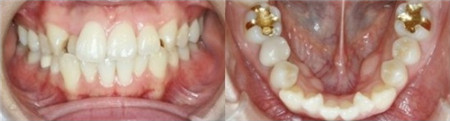

矫正之前,我的虎牙很严重,参差不齐,上下牙齿排列也不整齐,笑的时候要挡着嘴巴。

先给大家看自拍照,治疗之前我有虎牙,小时候觉得这样很可爱,但是20多岁了就显得有点尴尬了,看起来不够干净利索。矫正之后整体改变大。

虎牙的形成是由于在有限的口腔内,牙齿萌出时周边空间不足导致牙齿里进外出。

下面是我的牙齿矫正中不同阶段的变化: